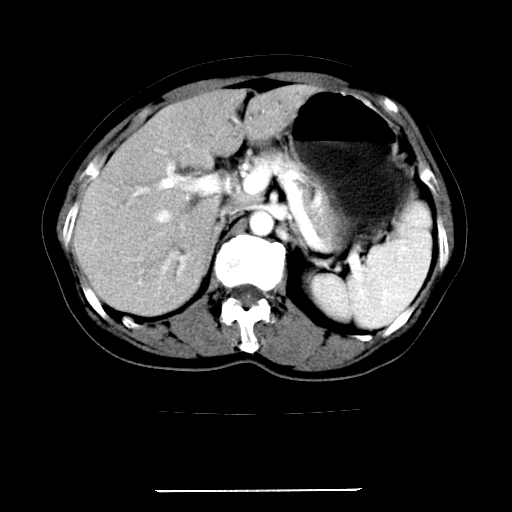

标题: CT22301:女,67岁,上腹部疼痛一周伴皮肤黄染,无发热。 [打印本页]

女,67岁,上腹部疼痛一周伴皮肤黄染,无发热。

左叶肝内胆管结石,并远端肝内胆管扩张。

考虑:肝内胆管结石继发肝内胆管扩张,右肾旋转不良。

肝内外胆管结石并肝内胆管扩张。

建议薄层观察,除外肝门部胆管细胞癌

考虑肝胆管癌;胰头占位?【形态失常,体积增大】

1、肝门高密度影下层面和胰头层面可见轻度胆管扩张,而静脉和延迟期均未见扫描完胰头,不能完全排除胰头占位。2、肝门部高密度影,考虑钙化或结石。

考虑肝门胆管癌伴门脉左支受侵包埋,建议mrcp进一步检查。